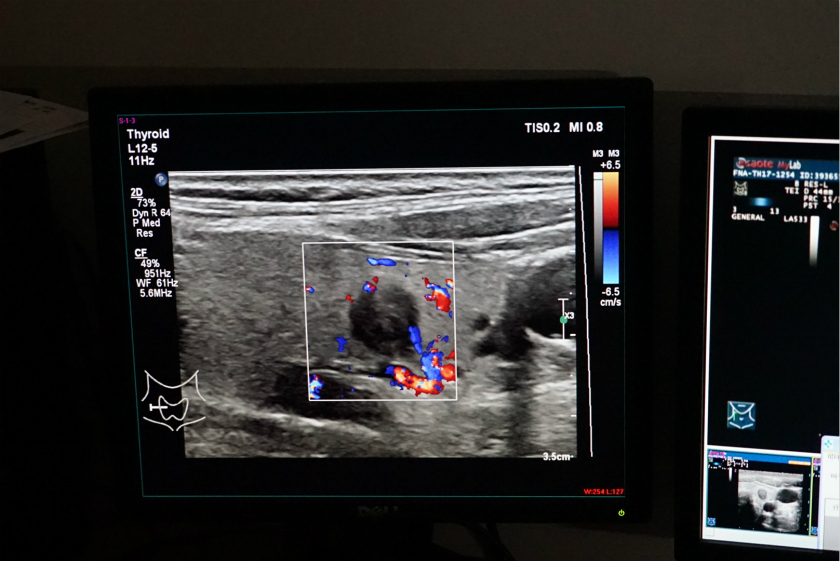

5月25日下午4点半,在浙江大学附属第一医院超声医学科排队就诊的人数依旧不少,就诊室墙边摆放着一套基于超声声象的甲状腺结节良恶性辅助诊断系统。

就在讲解过程中,一名中年妇女测试的数据已同步并显示到了屏幕中,主任医生介绍到,通过深度学习,系统能在检测后给出甲状腺结节的一切信息,例如绿色区域便是动态监测出结节的位置,而红色的部分显示是恶性结节。

“相比之前的诊断方式,这套超声声象甲状腺结节良恶性辅助诊断系统更直接了”主任医生告诉界面。